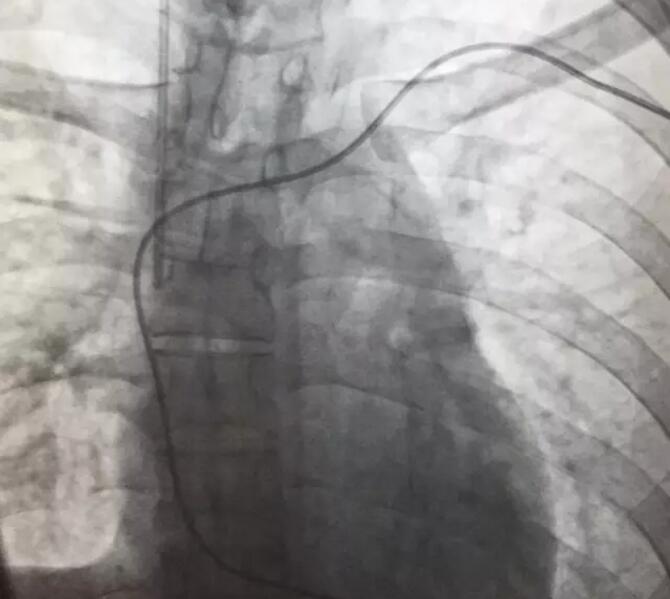

入院后,心内科的值班医生考虑,患者在院前曾出现抽搐、心跳停搏现象,心肌炎较为严重,心脏随时有再次发生停搏的可能,于是马上通知上级医生进行紧急会诊,专家会诊后决定,立即为病人紧急手术安装心脏保护装置-临时起搏器。

手术过程有惊无险,手术在介入科DSA引导下进行,在临时起搏导管送入到右心室时,病人突然出现神志不清、四肢抽搐,心电监护显示患者再次出现心室停搏,手术医生们临危不乱,果断为病人实施各项抢救措施的同时立即连接并启动起搏器。病人心跳马上恢复,随后转醒。经过差不多一个小时,患者顺利安装了临时心脏起搏器,并转入心内科重症监护病区密切观察和治疗。